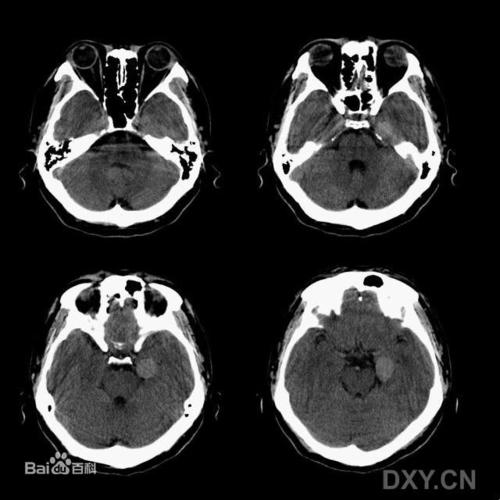

头颅ct图中显示右侧有个大大的脑膜瘤